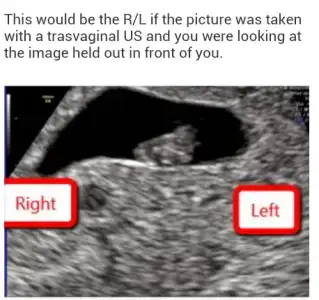

Ramzi teorisiyle ilgili bir onceki sayfada yorum yapmistim,plasentanin konumuna gore bir varsayim bu,rahmin sagindaysa erkek,soldaysa kiz diyor. %97 dogruluk iddia ediyor. Plasentanin konumunu biz pek bilemiyoruz usg ye bakip ama yolk kesesi oluyor belli bir haftaya kadar bebisin beslendigi, o da plasenta tarafinda oluyor. Senin alttaki fotoda bebisin disinda yusyuvarlak bisey dahagorunuyor dikkat edersen kafa gibi..sana gore sola yakin duruyor ama vajinal oldugu icin ultrason o aslinda sag...ve plasenta da buyuk ihtimal orda ve bebis erkek. Ben bebisin konumuna bakmiyorum, ve bunu da ben demiyorumm haberiniz olsun :) bu bir teori sonucta, Rabbim herkese gönlundekini oncelikle saglikli ve hayirli olmak kaydiyla nasip etsin,...umarim aciklayabilmisimdir.